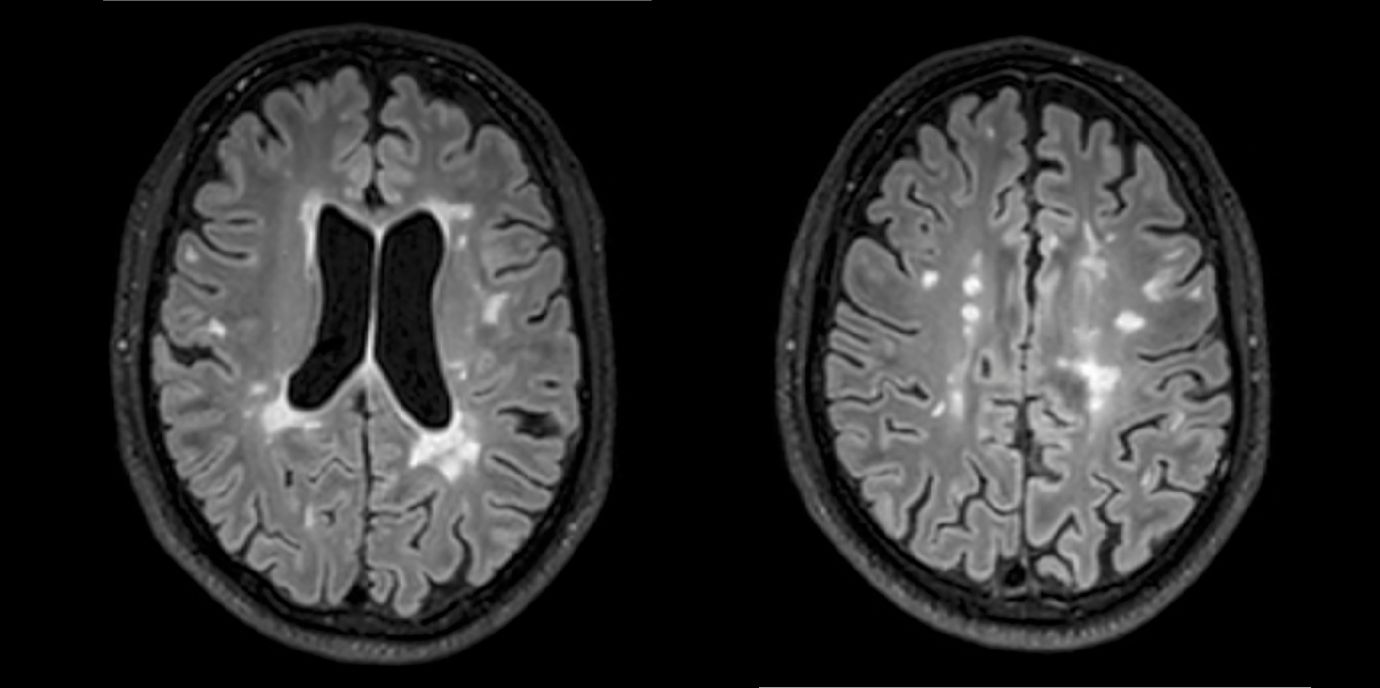

Abseits klinischer Symptome, die von Einschränkungen des Sehvermögens bis hin zu Lähmungserscheinungen ein breites Spektrum umfassen, kann die Krankheitsaktivität bei MS auch bildgebend dargestellt werden. „Der Nachweis entzündlicher Läsionen im Gehirn mittels MRTerlaubt auch eine Einschätzung geringerer Krankheitsaktivität, denn vermeintlich stabile Patient:innen können trotz Therapie weiterhin neue, klinisch stumme, entzündliche Veränderungen entwickeln“, weiß Neuroimmunologe Harald Hegen, der an der Innsbrucker Univ.-Klinik für Neurologie bereits seit vielen Jahren zu MS forscht.

In die Studienkohorte wurden 131 MS-Patient:innen aus MS-Zentren in Österreich und der Schweiz eingeschlossen, die unter einer gering- bis moderat-effektiven Immuntherapie zwölf Monate lang klinisch stabil waren und dann einer MRT unterzogen wurden. „Wir konnten zeigen, dass Patient:innen mit schubförmiger MS, die unter Immuntherapie zwei oder mehr neue entzündliche MRT-Läsionen innerhalb eines Jahres entwickeln, auch bei klinischer Stabilität, also ohne Symptome, von einem Wechsel auf eine hoch-effektive Immuntherapie profitieren“, beschreibt Erstautor Gabriel Bsteh von der Medizinischen Universität Wien die zentrale Erkenntnis. Damit liefert die Studie eine für den klinischen Alltag wichtige Erkenntnis, die für die individuelle Therapieanpassung genutzt werden sollte.

„Nachdem Läsionen oft schon vor dem Auftreten klinischer Symptome in der MRT sichtbar sind, ermöglicht eine bildgebende Kontrolle bei Patient:innen mit einer gering- bis moderat-effektiven Therapie ein frühes Eingreifen in den individuellen Krankheitsverlauf“, betont Studienleiter Harald Hegen. In der Studienkohorte waren rund 40 Prozent der Patient:innen klinisch stabil, zeigten allerdings in der MRT schon eine oder mehrere Läsionen. Bislang war in der klinischen Praxis eine Therapieverstärkung nur nach Auftreten klinisch manifester Symptome angezeigt.